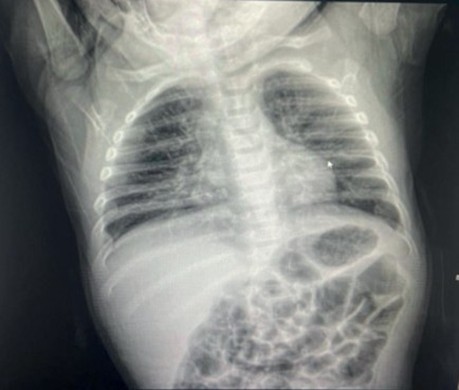

Se realizó radiografía de tórax (véase Figura 1) en proyección posteroante rior. No se observaron alteraciones de partes blandas. Las estructuras óseas mostraron aplanamiento de arcos costales, atribuido a la edad y posición de la paciente. Se evidenciaron infiltrados perihiliares bilaterales y aumento de las marcas broncovasculares, así como mayor radiolucidez pericárdica (“signo del corazón claro”).

Figura 1. Radiografía anteroposterior de tórax

Fuente: expediente clínico.